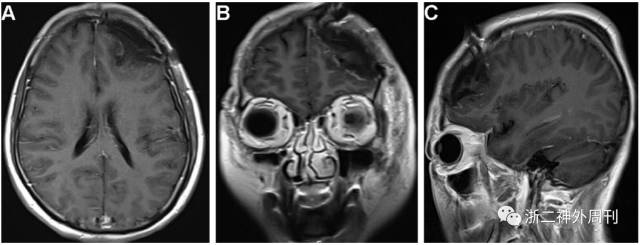

术后影像(图3):肿瘤全切除

图3. 术后复查头颅磁共振增强扫描轴位(A)、冠状位(B)、矢状位(C)